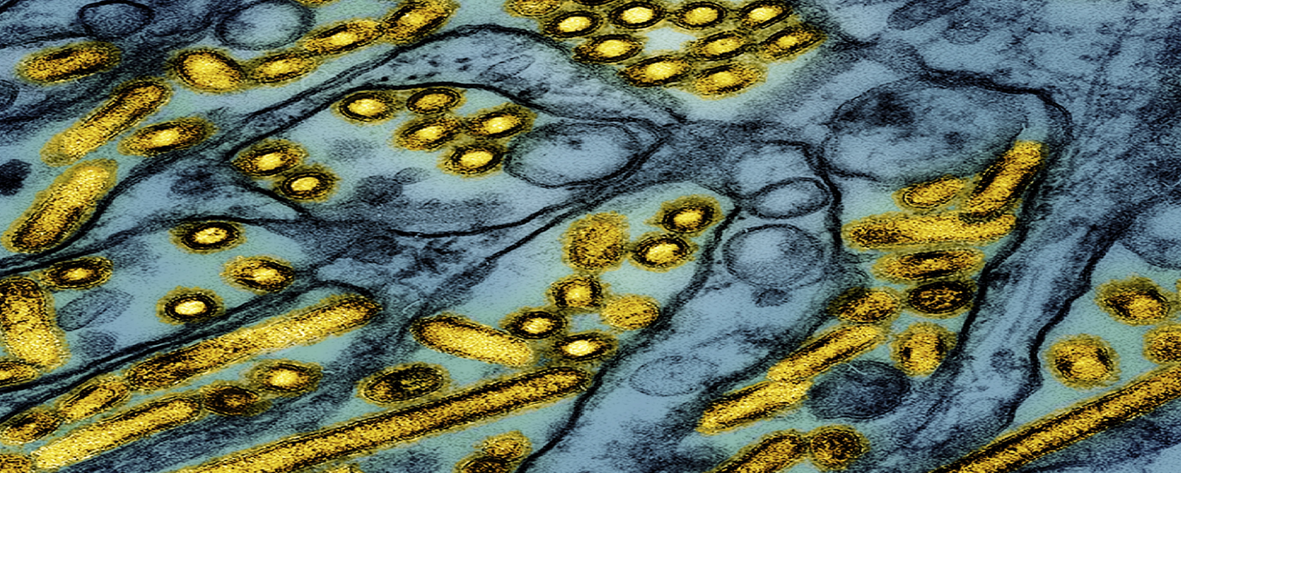

The colorized electron microscope image released by the National Institute of Allergy and Infectious Diseases shows avian influenza A H5N1 virus particles -- yellow -- grown in Madin-Darby Canine Kidney epithelial cells -- blue.